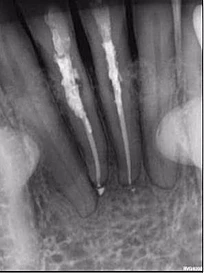

Một phụ nữ 54 tuổi với tiền sử chấn thương tới phòng khám với lý do răng 41 đau và áp xe gây khó khăn khi ăn nhai. Trên XQ 2 chiều thấy tổn thương tiêu ở răng 41 và áp xe ở răng 42 (Hình 1 và 2), rất khó để biết phạm vi nội tiêu theo hướng ngoài – trong. Tổn thương trông có vẻ rộng, nhưng có phá ra phía ngoài hay trong không? May mắn thay, phim chụp từ máy CS 8100 cho thấy nội tiêu chỉ nằm trong phạm vi ống tủy (hình 3 – 5), do đó tôi tự tin rằng điều trị tủy có thể giải quyết vấn đề của bệnh nhân, hai răng này sau đó được đặt Ca(OH)2 rồi trám bít (hình 6 và 7)

Hình 1: Phim XQ 2 chiều trước điều trị

Hình 2: XQ 2 chiều trước điều trị (ảnh chụp ở phòng khám khác